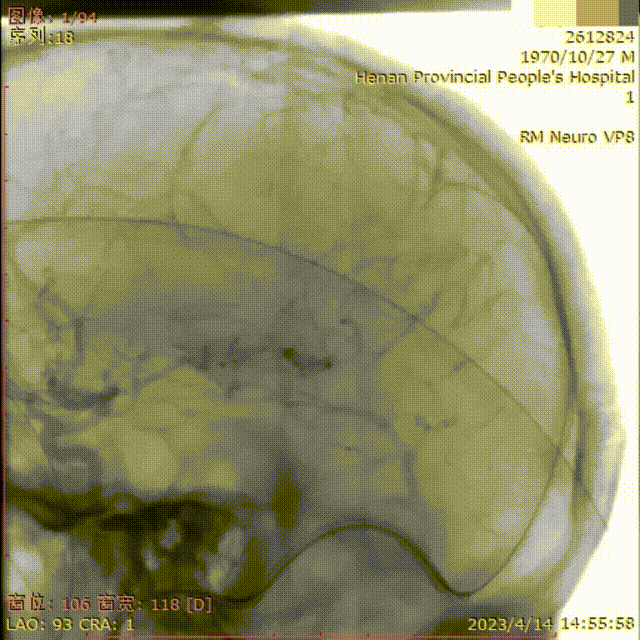

北斗SS™神经血管导丝导引下,顺利将取栓装置引入至上矢状窦内。

北斗SS™神经血管导丝辅助下,将取栓装置进一步引入至上矢状窦前1/3处。

取出大量静脉窦内血栓。

术后造影显示上矢状窦较前明显改善。